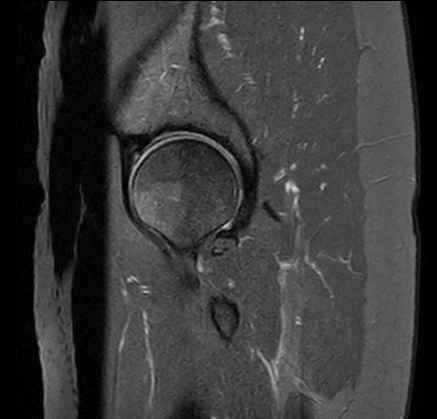

Beispiele von MRT Aufnahmen der Hüfte